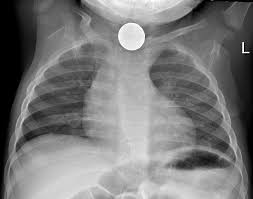

pada pemeriksaan di radiologi tidak semua pasien yang datang untuk foto rontgen dalam ke adaan yang umum atau 'normal' 'terkadang kita dihadapkan dengan situasi dengan pasien yang tidak biasa atau 'tidak normal' tetapi disinilah salah satu tantangan dalam menghadapinya , mungkin ini beberapa contoh kasus yang tidak biasanya..